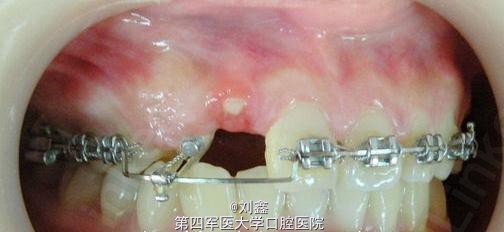

患者女 17岁 主诉:上尖牙未萌出及上前牙折断求矫治

1.右上乳尖牙滞留,右上尖牙近中阻生。 2.右上侧切牙冠折。 3.左上尖牙反合及上前牙不齐。

牵引埋伏13,预留12间隙待矫治结束后行桩核冠修复。 矫治步骤: 1.直丝弓矫正器排挤上颌牙。 2.改良上颌Nance托加强上后牙支抗及牵引埋伏13。 3.改良Hawlays式保持器保持。 4.12固定修复

13埋伏于12与11之间,在牵引13时需注意其牵引的方向。